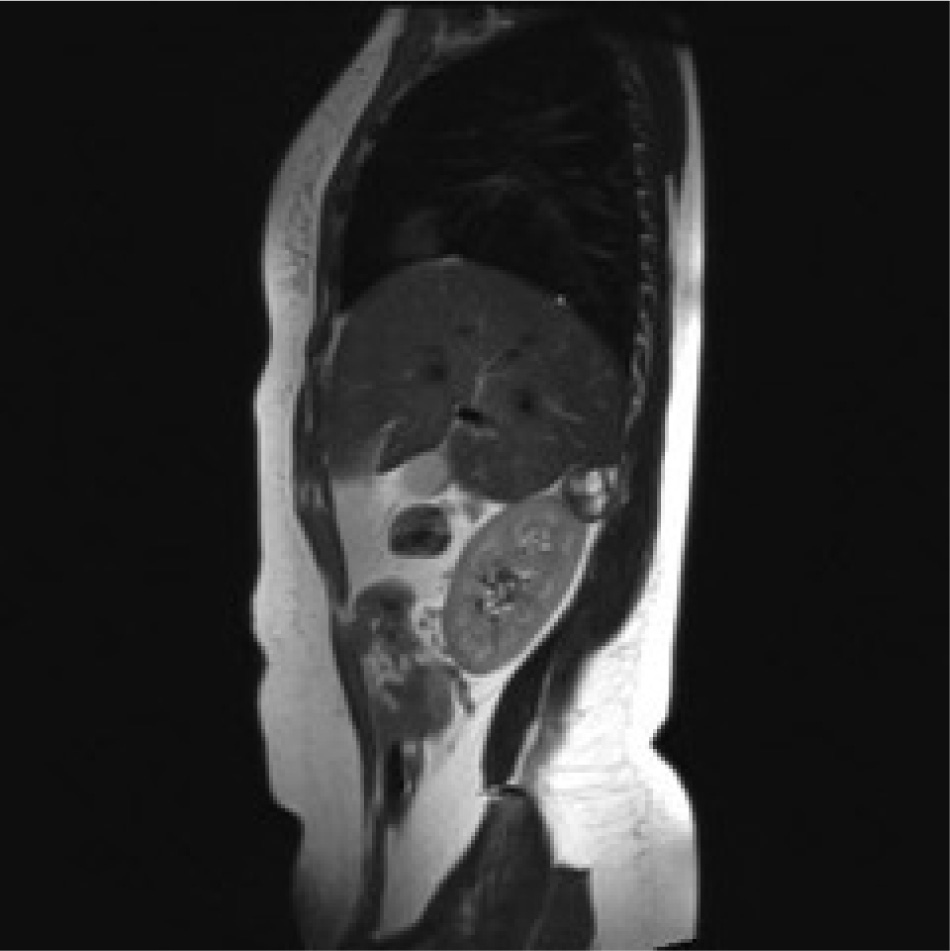

A 78-years old Moroccan woman was admitted to our department for a right flank pain without any other relevant symptoms or signs; she referred to only a light pain radiating to the epigastric region. The pain had started eight or ten months previously, she had no nausea or vomiting, she was afebrile and her vital signs were normal. She denied any contact with dogs or sheep and she had moved from Morocco to Italy in 2009. She was unemployed. Her physical examination was normal, without any significant signs or symptoms, which could suggest retroperitoneal abdominal masses. When she was a child she had the common infective diseases and at the moment of physical examination she had only an iron deficiency anemia. She underwent two Caesarean Births in 2009 and 2012. We performed routine laboratory exams on her, such as hemocromocitometric panel, major biochemical values and principal enzymes; there was no pathological alteration. She underwent ultrasound abdominal exam so we found a strange ovoidal hypoechoic formation in the right adrenal gland space; it was four centimetres in maximum diameter, and there were no signs of peripheral or central vascularization at Doppler’s exam; it was impossible to establish a sure diagnosis so we proposed a CT scan of the abdomen. The CT scan showed a solid mass of maximum diameter 5 cm, with a light peripheral vascularization and degenerative cystic areas; it had no clear linkage with either liver or with right adrenal gland. Therefore we decided to admit her to perform other imaging and laboratory exams; in fact we required an abdominal MRI which showed: “mass of 34 x 27 mm with a central cyst composed of a multilocular structure, there are signs of parietal vascularization and there aren’t signs of a clear dissection plane from kidney and liver”(image 1,2,3,4). Despite this we continued with a screening exam for HD such as indirect hemaglutination test and also hormonal exams both for adrenal cortex hormones and medullar catecholamines; all these exams were negative. We decided to perform a surgical approach to this mass, because we had to have a sure histological diagnosis of the mass; we gained the informed consent for surgical procedure. We set up the patient on the operating table in lateral left decubitus, we obtained a pneumoperitoneum with open technique and after an accurate exploration of abdominal cavity placed another three trocars to complete the procedure. We gained access to the retroperitoneal space with the same surgical steps of a laparoscopic adrenalectomy. There were significant adhesions between the unknown mass and the liver, kidney and adrenal gland. The mass was removed after a dissection through an unclear plane between liver and lesion. We extracted it into a laparoscopic bag from the access in right flank (image 5). The postoperative course was regular, without relevant complications. Unfortunately the definitive histological report was unclear. There was a significant rise in IG indirect hemagglutination one month after the surgical procedure (Indirect Haemoagglutination Assay was 1:600). Therefore we called a specialist for expert advice and finally we reached a conclusive diagnosis: Hydatid cyst localized in the retroperitoneal right adrenal gland space. Now the patient is in good health; even so, we have prescribed her a prophylactic drug treatment with albendazole.

Rm scan T1weighted sagittal image showing the adrenal mass